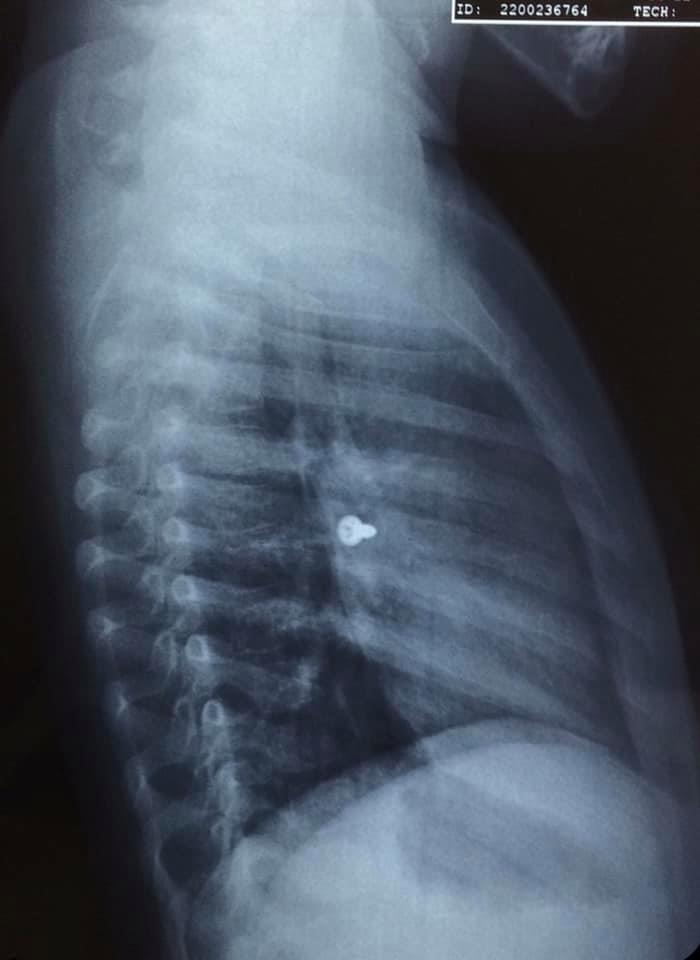

Αμέσως έβγαλε ακτινογραφίες, που έδειξαν πως η βίδα βρισκόταν στον αριστερό του πνεύμονα, με τις εικόνες να είναι σοκαριστικές.

Οι γιατροί οδήγησαν το κορίτσι στο χειρουργείο και μετά από αρκετή ώρα κατάφεραν να αφαιρέσουν την βίδα.

Ο κ. Προκοπάκης σε ανάρτησή του στα social media ανέφερε: «Πολύ επείγον χειρουργείο! Πριν από λίγο. Αφαίρεση βίδας από αριστερό βρογχικό δέντρο τρίχρονου κοριτσιού. Πολύ επικίνδυνο…».